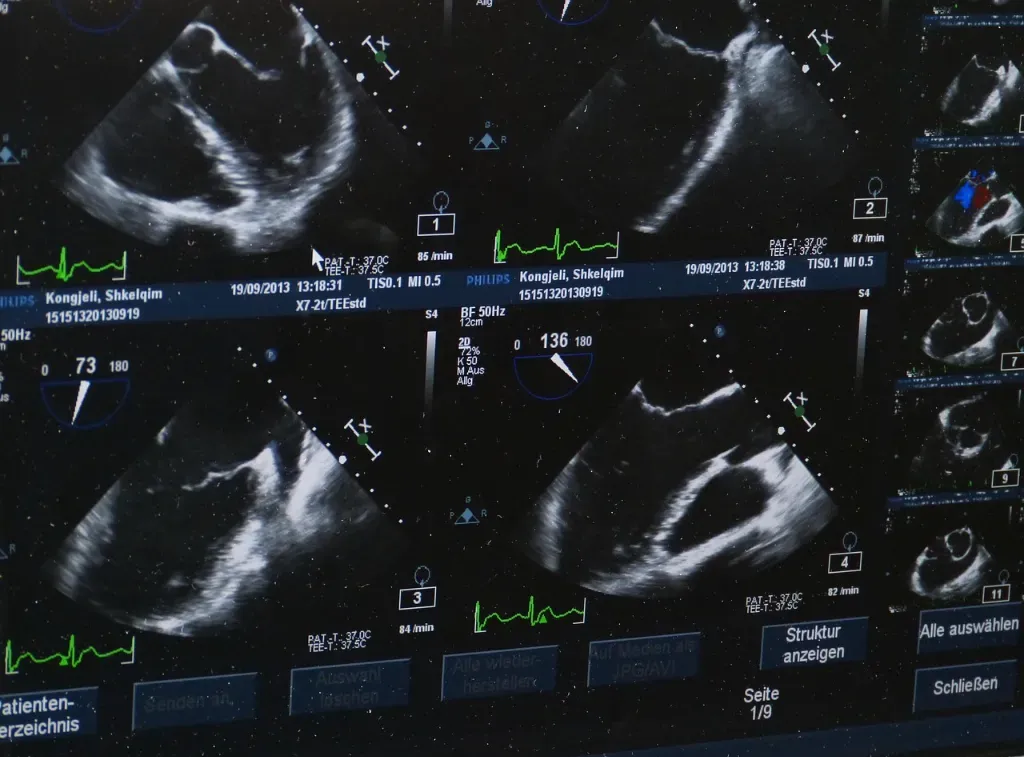

Żel do USG to specjalistyczny preparat, który odgrywa niezwykle istotną rolę podczas wykonywania badań ultrasonograficznych. Choć może się wydawać, że to jedynie niepozorny środek, jego funkcja jest kluczowa dla prawidłowego przebiegu i jakości badania. W medycynie wykorzystuje się go, aby zapewnić odpowiedni kontakt między głowicą aparatu USG a skórą pacjenta. Dlaczego to takie ważne? Ponieważ ultradźwięki, które są podstawą działania ultrasonografu, potrzebują medium przewodzącego, które eliminowałoby powietrze i pozwalało na swobodne przenikanie fal dźwiękowych.